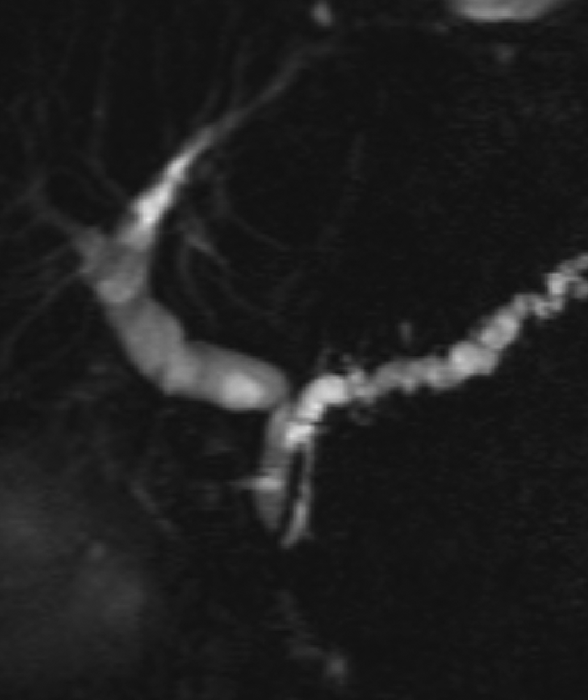

Figure 2

Coronal oblique thick‑slab MRCP image shows 2 MRCP signs that suggest the mass may be inflammatory in nature rather than neoplastic: (a) the “duct penetrating sign” (the pancreatic duct runs through the mass and is not interrupted), and (b) the “attraction sign” (the common bile duct is bent at a 90° angle and attracted to the mass). The final diagnosis was indeed inflammatory pseudomass.